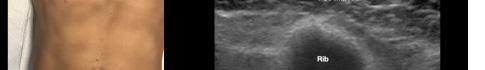

115 Point-of-care Ultrasound Identification of Hepatic Abscess in the Emergency Department

M Blomquist, T Brinkerhoff, D Weech, H Choi